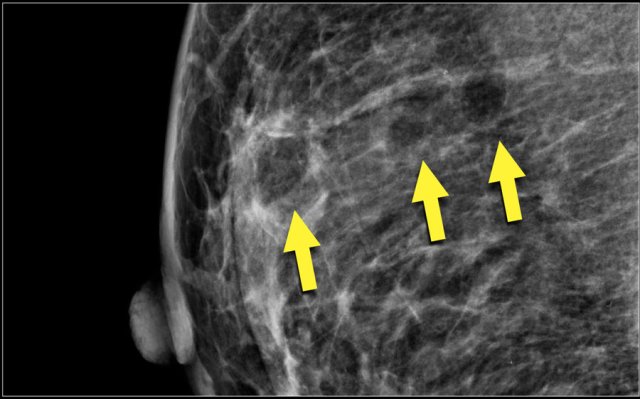

Study the images and describe the calcifications.

Then continue reading.

The findings are:

- Morphology: some are coarse heterogenous and some look more like fine pleomorphic.

- Distribution: Some calcifications are in a group ( <2cm) and some are in a regional distribution ( >2cm), but not in a segmental or linear arrangement.

This proved to be multifocal DCIS with areas of invasive carcinoma.